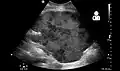

Imaging

Postoperatively, kidneys are periodically assessed by ultrasound to assess for the imaging and physiologic changes that accompany transplant rejection. Imaging also allows evaluation of supportive structures such as the anastomosed transplant artery, vein, and ureter, to ensure they are stable in appearance.

The major sonographic scale in quantitative ultrasound assessment is with a multipoint assessment of the resistive index (RI), beginning at the main renal artery and vein and ending at the arcuate vessels. It is calculated as follows:

RI = (peak systolic velocity – end diastolic velocity ) / peak systolic velocity

The normal value is ≈ 0.60, with 0.70 being the upper limit of normal.[69][70]